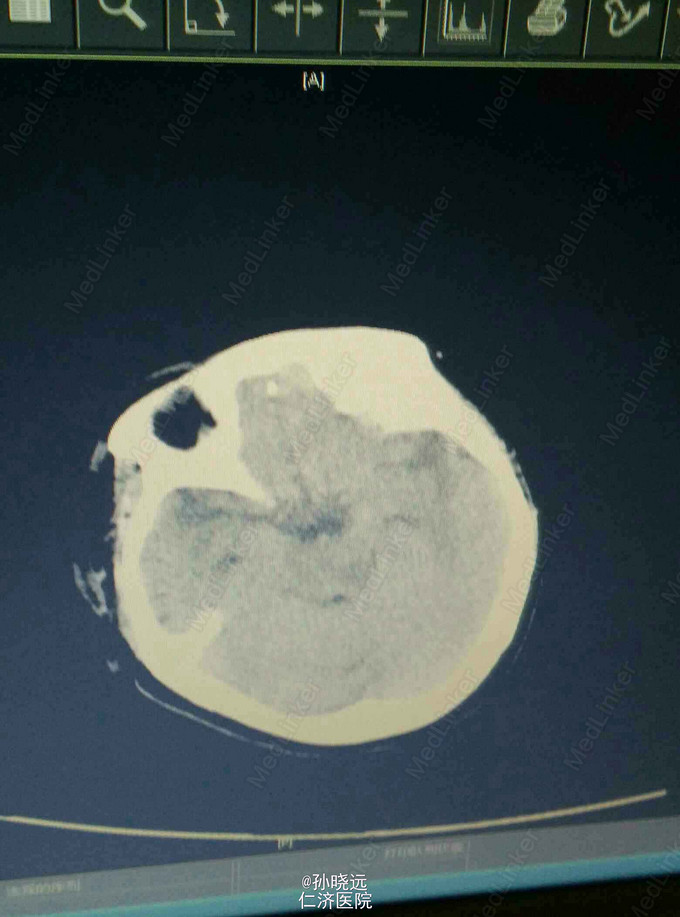

中年女性。主诉:头晕三天,发热伴神志不清1天。 患者于三天前出现持续性头晕,无恶心、呕吐,无视物旋转,来院就诊,查头颅MRI未见异常,予桂哌齐特、长春西汀、硫辛酸治疗,症状无好转。1天前出现高热,最高39.5℃,无咳嗽、气促,再次来院就诊,查血常规:WBC:5.85*10^9/L,N:71.8%,CRP正常,予退热,阿奇霉素等治疗,今日凌晨出现神志不清,无抽搐、恶心、呕吐,头颅CT示两侧颞底部不规则斑点样密度增高影并周围低密度灶,考虑脑炎合并灶性出血,予更昔洛韦、醒脑静、喜炎平、奥美拉唑、甘露醇治疗。后出现氧饱和度下降,予气管插管有创呼吸机辅助通气。 既往史:曾有高血压病史,未应用降压药。

诊断:脑炎。脑出血。 治疗:甲强龙抗炎,更昔洛韦,青霉素钠抗感染,降压,甘露醇、甘油果糖、白蛋白、拖拉塞米里降颅压,呼吸机辅助通气等对症治疗。

腰穿是: 脑脊液生化:葡萄糖:12.18mmol/L,CL:110.9mmol/L,蛋白:222.4mg/dl, 脑脊液常规:淡黄,微混。红细胞:1000*10^6/L,白细胞:1059*10^6/L,潘氏试验阳性(++++),嗜中性粒细胞12%,淋巴细胞:80%,单核细胞8%,凝块无,细菌未找到。 予加用血必净,加强抗感染等治疗。 患者目前仍昏迷,正进行高压氧仓治疗。这是最近一次复查的头颅CT。